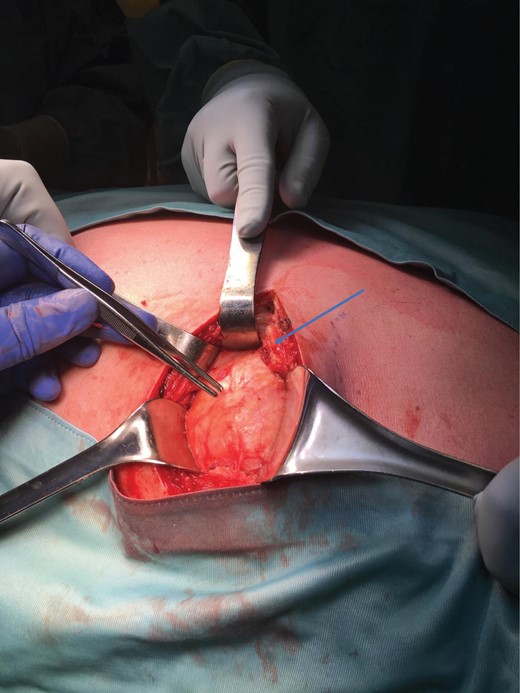

Surgery was uneventful but the tumour was quite deep below the lattisimus dorsi and serratus anterior muscles, and lying on the posterior rib cage (Figs 5–7).

Tumour exposure(forceps) below the lattisimus dorsi (blue arrow).